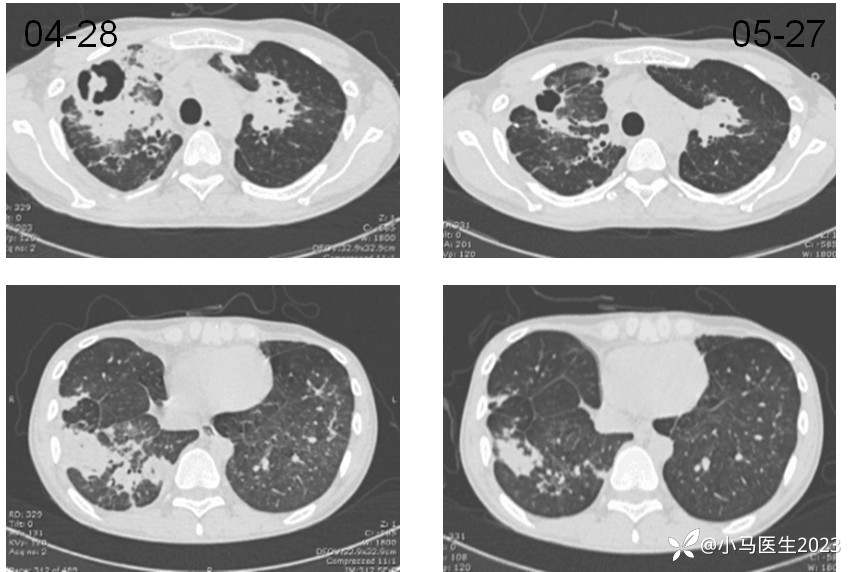

2021-04-28胸部CT进展,空洞形成

胸部CT对比

05-12

05-27

对比